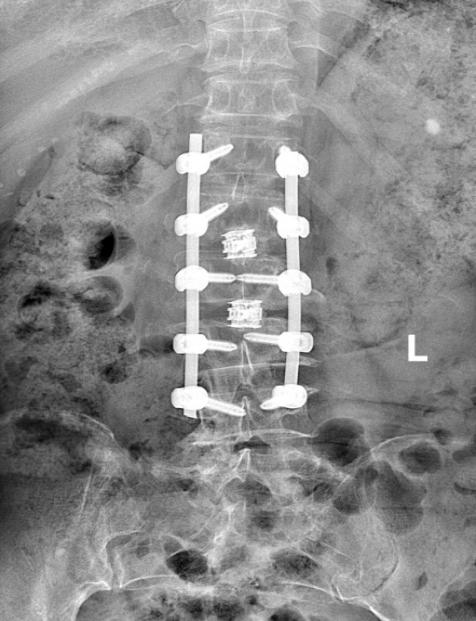

四师总医院脊柱外科团队在充分评估患者病情及风险后,决定在脊柱内镜辅助下进行脊柱侧弯矫形手术。手术利用内镜微创优势,完成多个间隙的微创减压,既减少创伤,又避免额外输血。术后患者恢复良好,疼痛缓解,已能正常站立行走,生活质量显著提升。

“将脊柱内镜微创优势融入常规手术,可缩小创伤、加速康复,并且手术过程中无需输血。”四师总医院骨科中心党支部书记、可克达拉院区骨科主任郑勇介绍道。

此次手术成功标志着伊犁河谷脊柱外科领域取得重大突破,为脊柱侧弯患者带来新希望。该创新术式以微创、精准特点降低风险,提升手术安全性与有效性,促进术后康复。